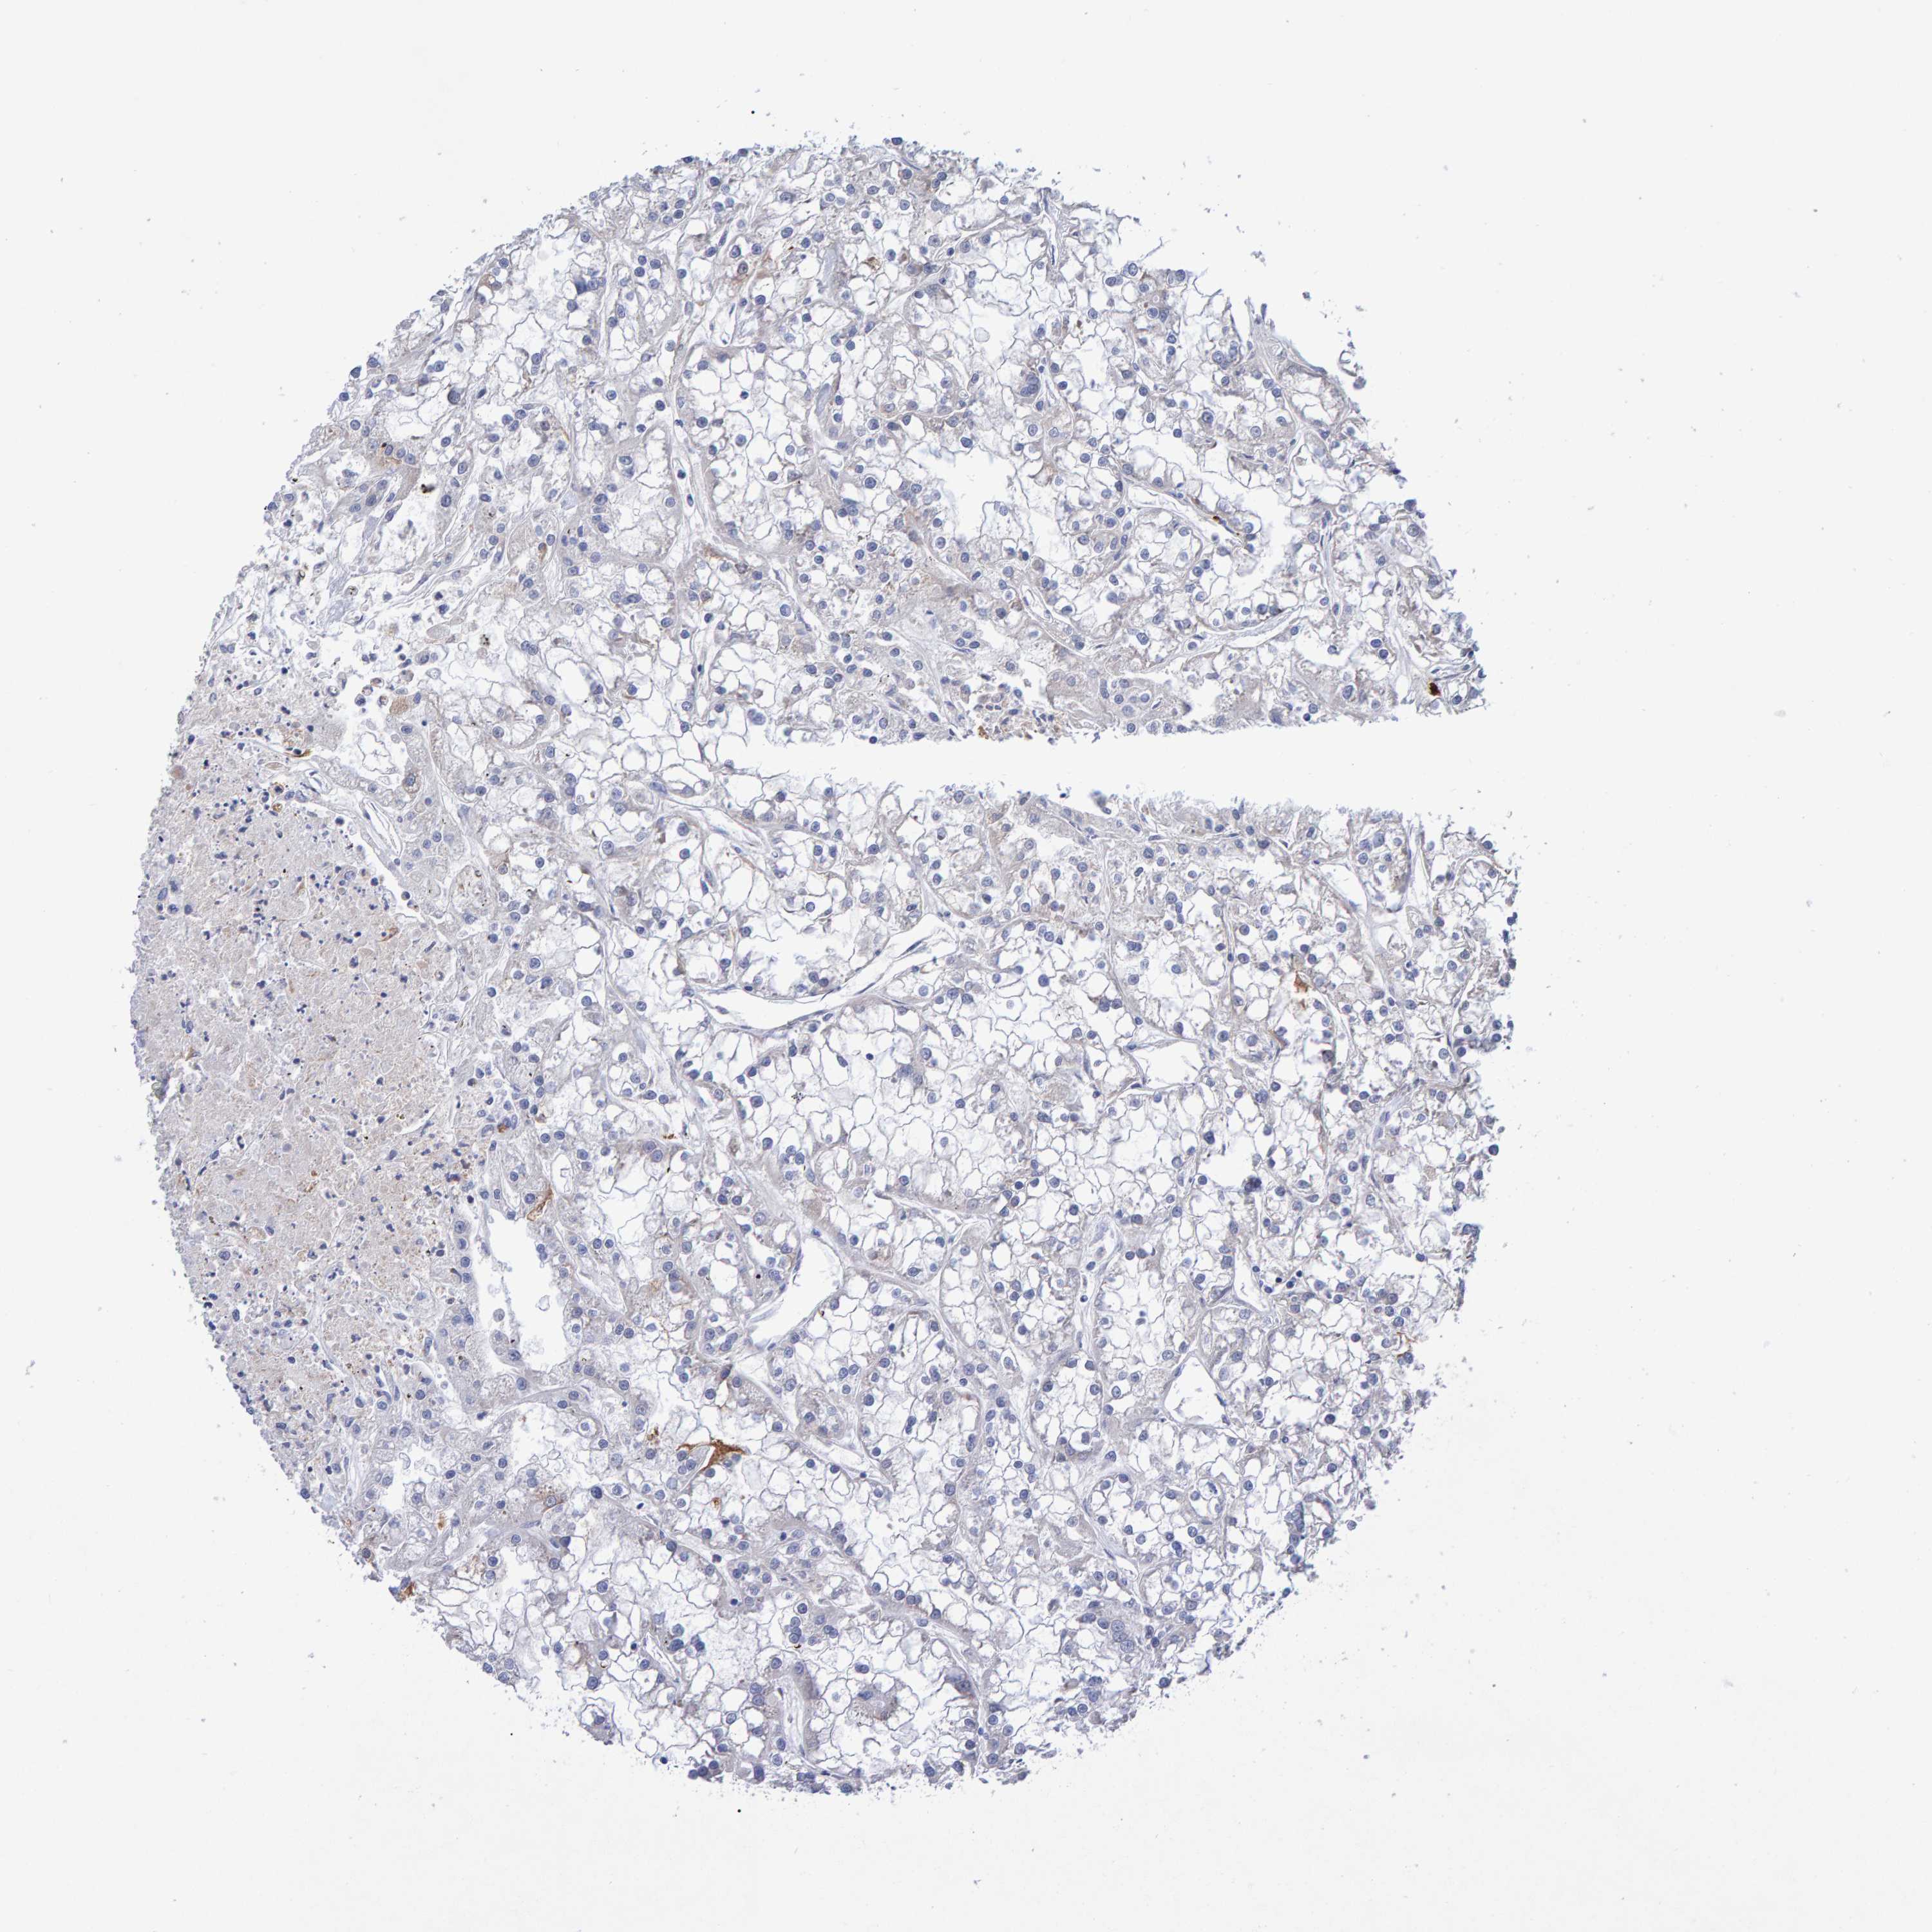

KIDNEY RENAL CLEAR CELL CARCINOMA (VALIDATION) - Interactive survival scatter ploti

The Survival Scatter plot shows the clinical status (i.e. dead or alive) for all individuals in the patient cohort, based on the same data that underlies the corresponding Kaplan-Meier plots. Patients that are alive at last time for follow-up are shown in blue and patients who have died during the study are shown in red.

The x-axis shows the expression levels (FPKM) of the investigated gene in the tumor tissue at the time of diagnosis. The y-axis shows the follow-up time after diagnosis (years). Both axes are complimented with kernel density curves demonstrating the data density over the axes. The top density plot shows the expression levels (FPKM) distribution among dead (red) and alive patients (blue). The right density plot shows the data density of the survived years of dead patients with high and low expression levels respectively, stratified using the cutoff indicated by the vertical dashed line through the Survival Scatter plot. This cutoff is automatically defined based on the FPKM cutoff that minimizes the p-score. The cutoff can be changed by dragging the vertical line or by entering a cutoff value in the square labeled "Current cut-off".

Under the Survival Scatter plot the p-score landscape (black curve; left axis) is shown together with dead median separation (red curve; right axis). Dead median separation is the difference in median mRNA expression between patients who have died with high and low expression, respectively. It is calculated as follows: median FPKM expression of dead patients with high expression - median FPKM expression of dead patients with low expression. This is intended to aid the user in visually exploring custom cutoffs and the associated p-scores and dead median separation.

Individual patient data is displayed and can be filtered by clicking on one or more of the category buttons on the top of the page. Categories describing expression level and patient information include: high, low, alive, dead, female, male and tumor stages. The scale of the x-axis can be toggled between linear and log-scale by clicking on the "x log" button. Mouse-over function shows TCGA ID, patient information and mRNA expression (FPKM) for each patient.

& Survival analysisi

Kaplan-Meier plots summarize results from analysis of correlation between mRNA expression level and patient survival. Patients were divided based on level of expression into one of the two groups "low" (under cut off) or "high" (over cut off). X-axis shows time for survival (years) and y-axis shows the probability of survival, where 1.0 corresponds to 100 percent.

EFR3A is not prognostic in Kidney Renal Clear Cell Carcinoma (validation)

Best expression cut offi

Based on the FPKM value of each gene, patients were classified into two groups and association between prognosis (survival) and gene expression (FPKM) was examined. The best expression cut-off refers the FPKM value that yields maximal difference with regard to survival between the two groups at the lowest log-rank P-value. Best expression cut-off was selected based on survival analysis .

When clicking on this number, the vertical dashed line indicating cut-off, the interactive survival plot, and the Kaplan-Meier curve will be adjusted to show results based on the best expression cut-off.

: 35.91

TCGA RNA samplesi

RNA-seq data is reported as average FPKM (number Fragments Per Kilobase of exon per Million reads), generated by the The Cancer Genome Atlas (TCGA) .

Normal distribution across the dataset is visualized with box plots, shown as median and 25th and 75th percentiles. Points are displayed as outliers if they are above or below 1.5 times the interquartile range. FPKM values of the individual samples are presented next to the box plot.

Average pTPM 35.3

Number of samples 100